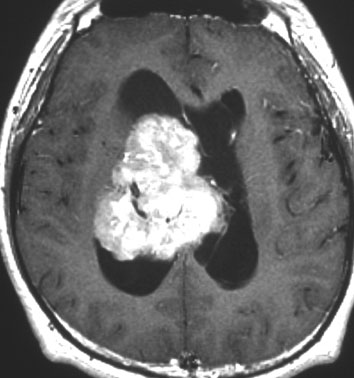

20代の男性の神経細胞腫です。側脳室の中のとても大きな腫瘍です。上段はガドリニウムという造影剤を入れた時のMRIです。下段の中央はCTですが,石灰化が見られます。脳外科の先生には,この脳室内腫瘍は一見transcallosal approach(経脳梁到達法)という手術で取れるように見えるかもしれませんが,そうではなくて,脳室の壁とくに上壁と側壁にくっついているのでなかなか取れません。この患者さんの場合は右の頭頂葉というところからtranscortical approach(経皮質到達法)で全摘出しました。後遺症もなく再発もなく術後10年が過ぎています。全部とれれば治ってしまう腫瘍です。